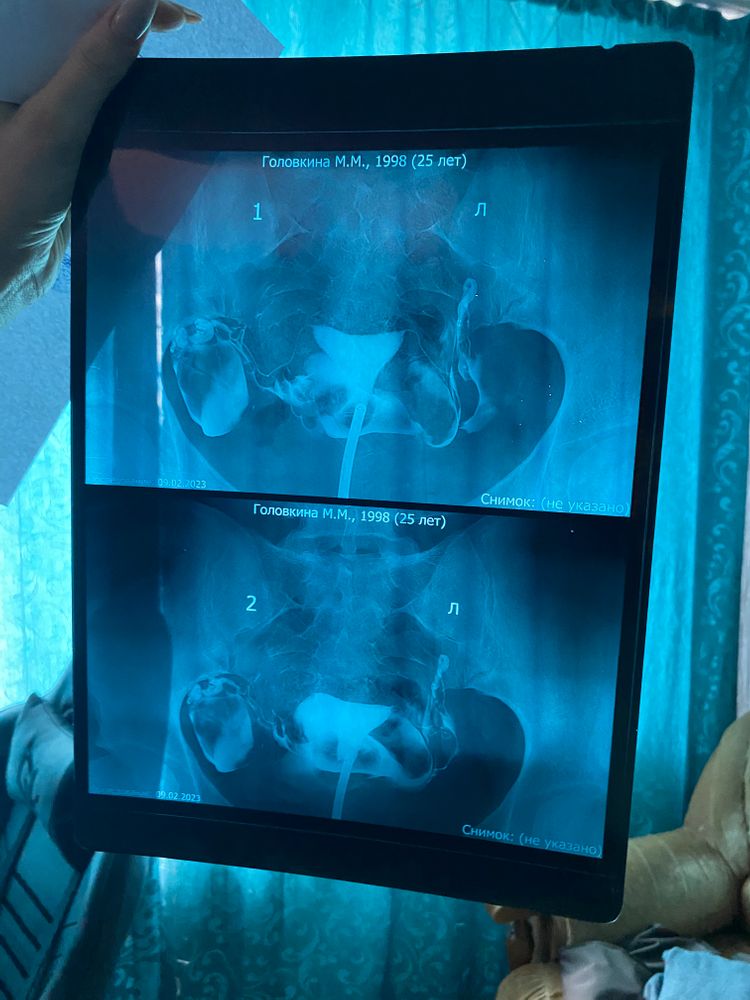

Гсг маточных труб

Добрый день! Подскажите пожалуйста, кто знает! Сделала Гсг , врач в клинике сказала, что все нормально и без отклонений , трубы проходимы , без загибов и не извилистые. Но как только принесла результаты в ЖК врачи сказали что трубы очень тонкие и в принципе не все хорошо по данному результату Гсг, но по этому поводу не нашла никакой информации в интернете. Скажите пожалуйста, может ли быть естественная беременность при данных трубах и есть ли необходимость идти с данными результатами к 3 гинекологу?

Марина Головкина, я к тому, что вашу «тонкость» труб должен оценивать не обычный гинеколог, а именно ре. А так, трубы как трубы, главное, что они проходимы. Спермик просто может недобегает пока что нужный) В любом случае, желаю вам скорейших //🙏